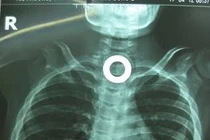

![]() |

| Chiếc muỗng nằm chếch một góc 30 độ trong bụng của nạn nhân và có thể lọt vào ruột bất cứ lúc nào. |

Sau khi kiểm tra, tình trạng của cô gái nghiêm trọng hơn nhiều so với những gì các bác sĩ nghĩ ban đầu. Bằng cách chụp X-Quang, bác sĩ đã phát hiện ra chiếc muỗng dài hơn 15cm trong bụng cô Wang, nằm chếch một góc 30 độ.

Theo bác sĩ, chiếc muỗng có thể trượt vào ruột bất cứ lúc nào. Nếu điều đó xảy ra, chiếc muỗng có thể làm thủng dạ dày và gây tổn thương nội tạng, thậm chí có thể dẫn tới tử vong. Từ đó, các bác sĩ đã quyết định lấy chiếc muỗng ra theo đường nó đã đi vào.